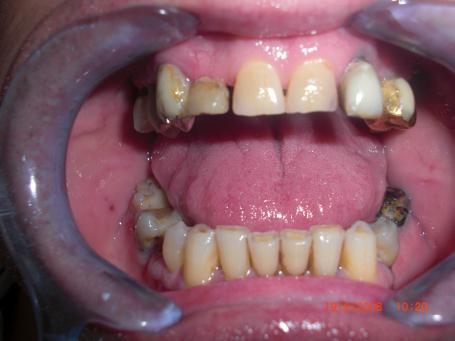

2°)Dépose des bridges iatrogènes

On dépose les couronnes dentaires inesthétiques pour placer des provisoires de 1er génération. Le début des soins (dévitalisation,reprise de traitement endodontiques,pivots,inlays cores...)peuvent débuter.